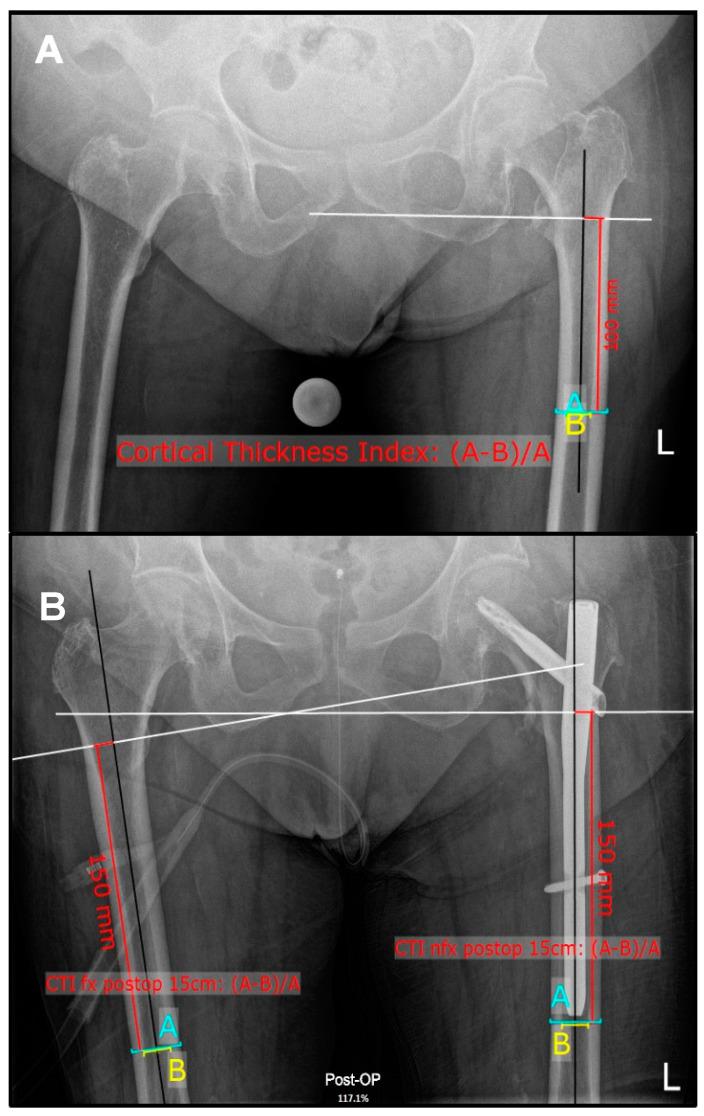

老年股骨近端骨折患者股骨皮质厚度指数的个体内差异

Osteoporosis is prevalent in the elderly and increases fracture risk. Bone density is commonly assessed using dual-energy X-ray absorptiometry (DEXA). The femoral cortical thickness index (CTI) also provides indirect information for osteoporosis. It remains unclear whether there are intra-individual differences and if a correlation to fracture risk of the CTI in fractured femora results due to fracture related malrotation during X-rays. The aim of this study was to investigate the individual bilateral CTI in patients with proximal femoral fractures. : A retrospective analysis of 200 surgically treated patients (100 trochanteric, 100 femoral neck fractures) was performed. Measurements included the bilateral CTI at 10 and 15 cm below the lesser trochanter. Analysis of the correlation of those examinations, in comparison to the contralateral CTI at 15 cm, and correlation of the CTI with the body mass index (BMI) and age was performed. : Results showed significant differences ( < 0.001) in bilateral CTIs for both fracture types at 15 cm with a strong inter-rater reliability (ICC > 0.9). There was no significant correlation between age and CTI, as well as BMI and CTI in both cohorts ( > 0.1). Sex-specific subgroup analyses revealed that females exhibited significant differences in CTI between fractured and non-fractured sides ( < 0.001). : In conclusion, CTI, and the modified CTI at 15 cm below the lesser trochanter in fractured proximal femora, is lower compared to the non-fractured side. The femoral CTI could help in daily clinical routines and circumstances, where more detailed risk prediction tools are lacking.

摘要

骨质疏松症在老年人中很普遍,会增加骨折风险。骨密度通常使用双能X线吸收法(DEXA)进行评估。股骨皮质厚度指数(CTI)也可为骨质疏松症提供间接信息。目前尚不清楚是否存在个体内差异,以及在X线检查期间,由于骨折相关的旋转不良,骨折股骨的CTI与骨折风险之间是否存在相关性。本研究的目的是调查股骨近端骨折患者的个体双侧CTI。:对200例接受手术治疗的患者(100例转子间骨折,100例股骨颈骨折)进行了回顾性分析。测量包括小转子下方10 cm和15 cm处的双侧CTI。分析了这些检查结果与对侧15 cm处CTI的相关性,以及CTI与体重指数(BMI)和年龄的相关性。:结果显示,两种骨折类型在15 cm处的双侧CTI存在显著差异(<0.001),评分者间可靠性强(ICC>0.9)。在两个队列中,年龄与CTI以及BMI与CTI之间均无显著相关性(>0.1)。按性别进行的亚组分析显示,女性骨折侧与未骨折侧的CTI存在显著差异(<0.001)。:总之,与未骨折侧相比,骨折近端股骨小转子下方15 cm处的CTI及改良CTI较低。在缺乏更详细风险预测工具的日常临床工作和情况下,股骨CTI可能会有所帮助。